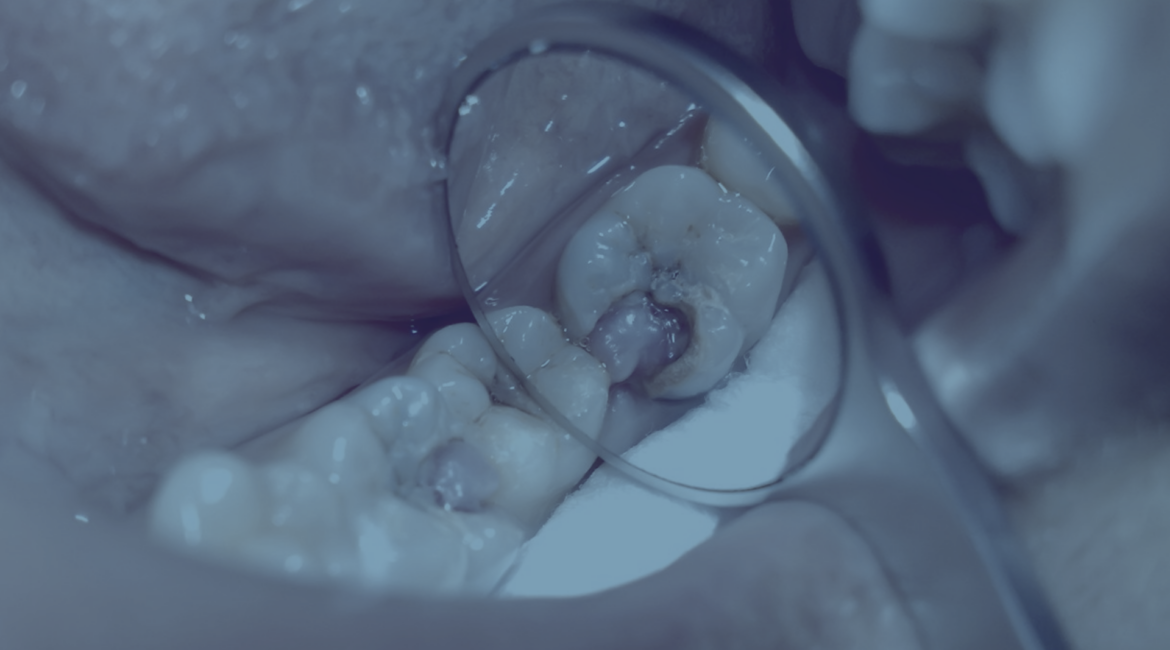

Пульпіт — це запалення пульпи зуба, або м’яких тканин, які містять кровоносні судини та нервові закінчення. Це захворювання зазвичай виникає як ускладнення глибокого карієсу, коли інфекція проникає в середину зуба через пошкоджену емаль і дентин. Найчастіше пульпіт супроводжується сильним пульсуючим болем, який не минає навіть після прийому знеболювальних препаратів.

Лікування пульпіту спрямоване на усунення запалення пульпи, очищення уражених тканин та збереження зуба. Для цього застосовують кілька сучасних методів. На початкових стадіях пульпіту використовується біологічний метод, який дозволяє зберегти життєздатність пульпи. У процесі лікування лікар видаляє пошкоджені тканини та накладає спеціальні препарати з вмістом кальцію, які сприяють загоєнню та регенерації пульпи.

Якщо запалення торкнулося лише верхньої частини пульпи, застосовують метод часткової ампутації. У цьому випадку уражену ділянку видаляють, проводять дезінфекцію порожнини зуба та заповнюють її лікувальними препаратами. При цьому тканини пульпи в кореневих каналах залишаються неушкодженими.

На пізніх стадіях пульпіту або у складних випадках призначається повне видалення пульпи, або депульпація. Ця процедура включає кілька етапів: застосування анестезії для усунення болю, видалення пульпи, очистку та пломбування кореневих каналів за допомогою біоінертних матеріалів. Герметизація кореневого каналу мінімізує ризик повторного зараження. Після депульпації зуб залишатиметься “мертвим”, але при належному догляді він може служити багато років.